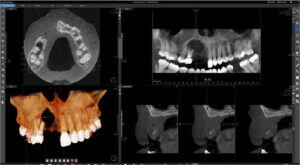

UR8 to UL8

Investigation of cystic lesion in upper right premolar area

KaVo OP 3D Vision V17

8x5cm FOV, 0.125mm voxel size, 120kV, 5mA, 7.4 seconds

There is a large unilocular moderately well-defined radiolucency, 23 x 15 x 14 mm extending from the UR5 apex to the midline but not invading the nasopalatine canal. There is a “through and through” destruction of the buccal and palatal cortical bony plates, as well as destruction of the alveolar bone ridge. The right maxillary sinus and floor of the nose are not involved. There is external root resorption of the UR4.

The lack of bone expansion, resorption of UR4 roots plus the “floating tooth” appearance of UR4 all suggest the possibility of malignancy. In a case such as this an urgent referral to an oral surgeon is recommended for biopsy to determine the diagnosis and rule out a malignancy.